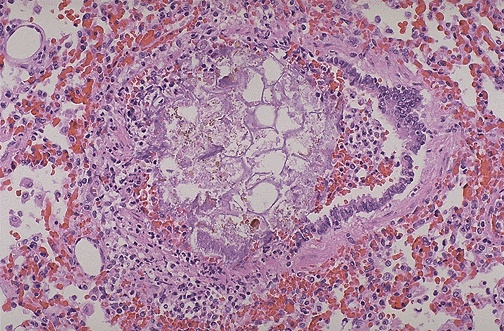

| Drowning may not produce extensive findings. In fact, in 10 to 15% of cases, intense laryngospasm may even prevent water from entering the lungs. In the case shown here, a child drowned in a fresh water canal, and some of the plant material in the water was aspirated into a bronchus. |